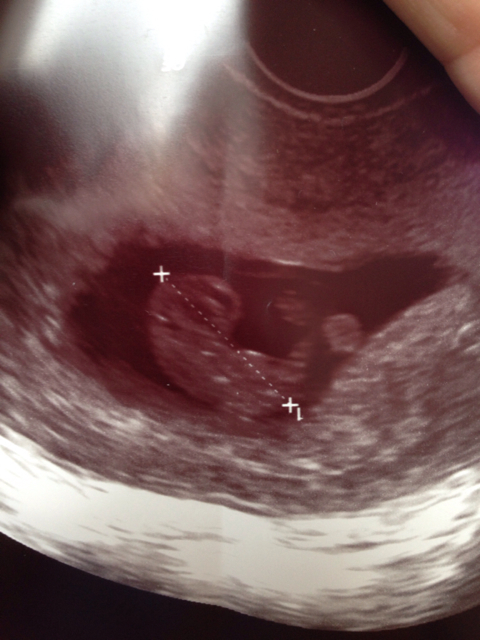

En liten oppdatering fra meg i denne dagboken også:)

Er i dag 4+3, 17 dpo. Fortsatt ikke tegn til noe rødt. Jeg syns testene har stagnert i fargen, legen ville jeg skal ta hcg måling pga de andre gangene jeg har mistet nå. Tok første på tirsdag, da 4+1(15dpo) og tok siste i dag. Får svar på den siste i morgen, og fikk svar på den fra tirsdag i dag. Hcg ble målt til 652. Det blir spennende å høre resultatet i morgen og høre om det har økt:).. Krysser fingrene:),

Dersom det er noen som er innom her som også engster seg for tester som stagnerer i styrken på streken. Det trenger visst ikke være noe feil. Fikk svar på siste hcg- måling nå. 15 dpo var den 652 og 17 dpo 1490.